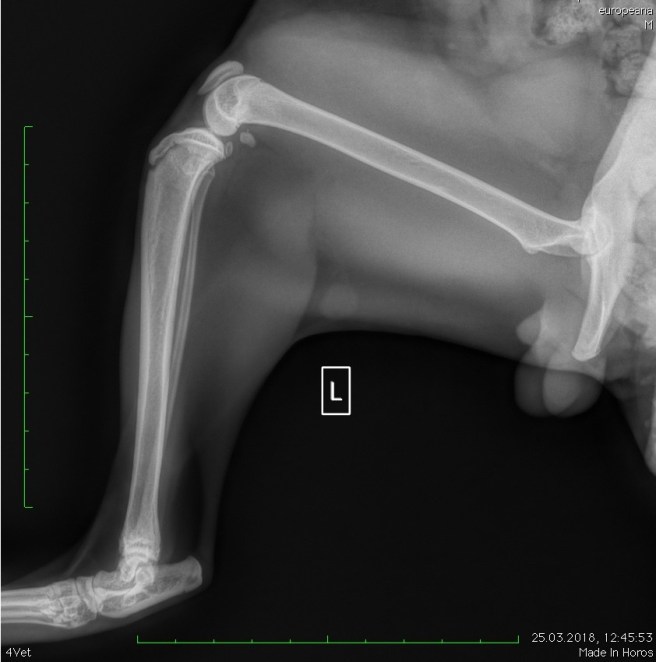

Vet: “It could be a fracture. The pain is so bad I can’t examine him properly. It’s best if we do some x-rays.”

Radiologist to Vincent: “Not a fracture/fissure/dislocation.”

Radiologist to Manoli: “Did you get bitten chasing kittens? You vagabond!”

Vet: “It looks like a torn muscle.”